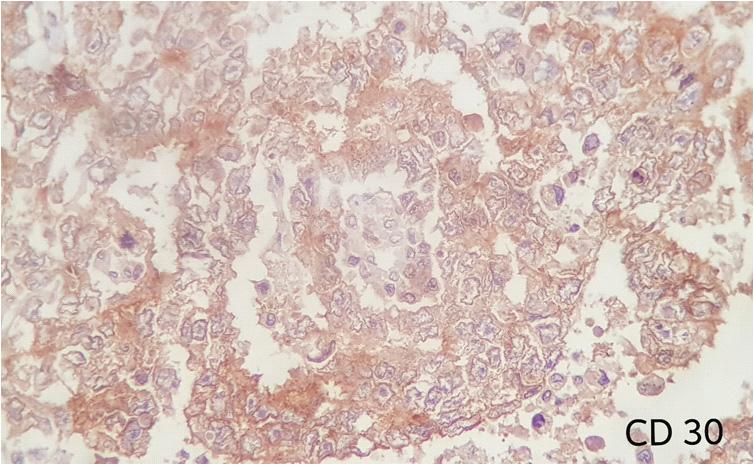

Ultrasound studies : Ultrasound showed cystic lesions in 17 patients and solid masses in three. Medial locations of a cystic retro-vesical mass were consistent with a prostatic utricle cyst (Fig 1) or abscess (Fig 2). Transrectal ultrasound was performed

additionally in eight patients to confirm the intraprostatic or extra-prostatic location of the cysts. Ultrasound revealed mixed echogenic masses in all the three patients with retro-vesical teratoma (Fig 3) which was difficult to differentiate from haematoma and four patients had cystic lesion contained hyperechoic material consistent with dermoid cyst but one letter on confirm on HPE was mullerian duct cyst with cystadenoma. A cystic extra-prostatic mass lateral to

Fig 4 — USG images of seminal vesicle cyst Fig 1 — USG images showed prostatic cyst Fig 3 — Radiological images of Teratoma (case no 5)

Fig 2 — Radiological pictures of Epidermoid cyst (case no 3) and Last MRI picture showed b/l seminal vesicle cyst (case no 4)